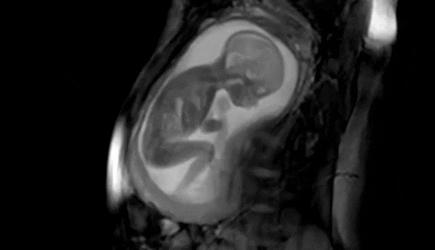

→胎儿大脑发育

研究发现,环境中BPA的暴露可能会影响妊娠期,胎儿大脑的发育。

涉及到雌激素调节、DNA修饰等等,这最终会对出生后孩子的社交行为、焦虑情绪产生影响。